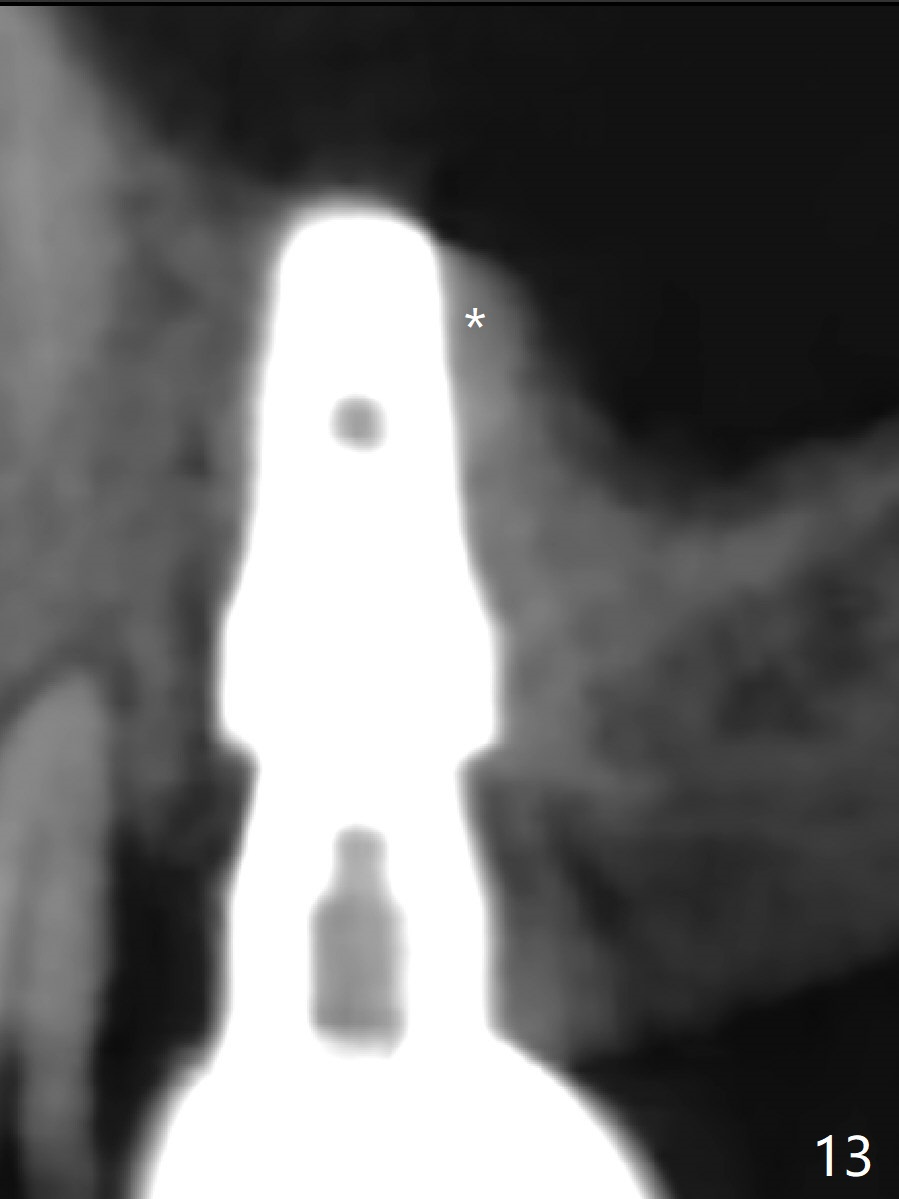

After extraction of the tooth #3 (Fig.1,2), the palatal socket (P) is as wide as the buccal one (B; Fig.3,4 (socket impression)), as compared to the roots), suggesting bone loss is more severe palatally than buccally. There is a circular area in the buccal slope of the palatal socket, in which the bone looks thin (purplish: presumably the sinus membrane underneath, Fig.5,7 (blue circle)). It appears that the palatal slope of the buccal socket (Fig.6, 7 red dashed line) is the most appropriate site for osteotomy (Fig.8). Prior to inserting 5.3 mm tap drill (Fig.9), the mesiopalatal region of the osteotomy (corresponding to the blue circle in Fig.7) perforates without sinus membrane tear. A small piece of Osteogen plug is placed in the perforation before inserting a 5.3x10 mm SM implant (Fig.10,11). Following placement of another piece of Osteogen plug in the palatal socket and of a 4.8x7(6) mm abutment, mineralized cortical and cancellous bone is placed (*). Collagen plug and an immediate provisional are used to close the socket opening. CT taken 11 months post cementation shows that the implant is placed within bony boundary, although buccally (Fig.12 B). Bone graft seems to heal in the sinus (Fig.13 (sagittal section),14 (coronal section) white * (Osteogen plug) and in the socket (brown * (allograft and Osteogen)).